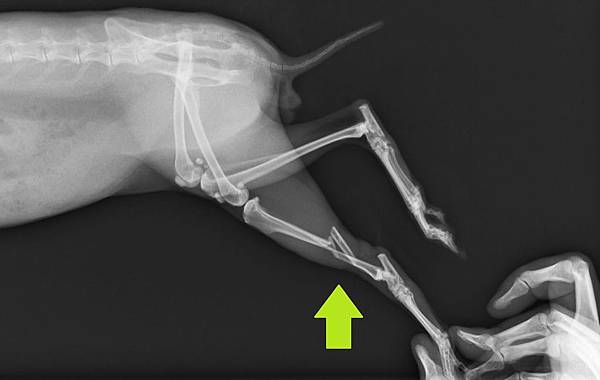

本病例為一隻年約2歲的兔子,主人發現時後肢已經無法負重,經兔友介紹後送至本院

拍攝X光後確認骨折部位為右後肢脛骨骨幹粉碎性骨折

70_203_20120329215626.0就診時脛骨側照

70_204_20120329215857.0 就診時脛骨正照